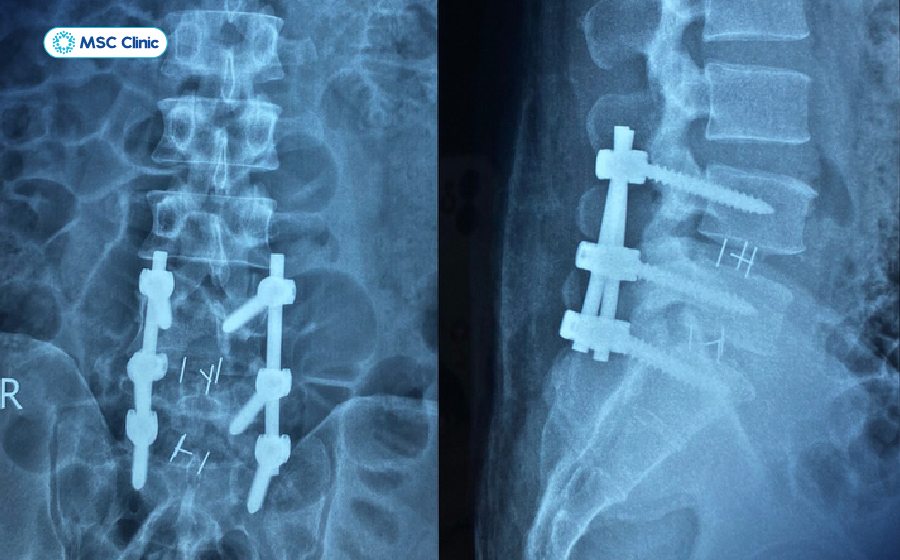

Hình ảnh X-quang sau phẫu thuật cố định cột sống dành cho các trường hợp nghiêm trọng

Phẫu thuật là lựa chọn cuối cùng khi đau lưng mỏi gối tê tay do nguyên nhân nghiêm trọng như thoát vị nặng hoặc chèn ép thần kinh kéo dài:

- Phẫu thuật xâm lấn tối thiểu: Ít đau, phục hồi nhanh, áp dụng cho thoát vị đĩa đệm hoặc chèn ép thần kinh.

- Phẫu thuật giải ép hoặc cố định cột sống: Dành cho các trường hợp nặng như hẹp ống sống, trượt đốt sống.